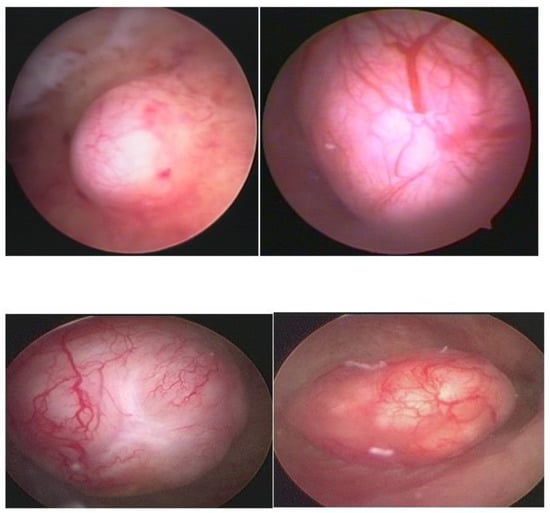

Hysteroscopy, as a method of direct visualization of the uterine cavity, offers all possible information about the intracavitary portion of the submucous myoma and a good assessment of the portion of the myoma, which is found in the myometrium, intramural portion. Thus, with hysteroscopy, it is possible to classify the submucous myoma and assess the need for other imaging methods. Another important function of hysteroscopy is to rule out other intrauterine causes of bleeding and to carry out an anatomopathological study of the endometrium or of the identified lesions, so it should, whenever possible, be indicated in the investigation (Figure 1).

Figure 1. Submucous myoma—hysteroscopic view.